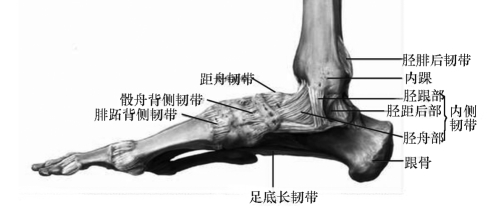

①学习韧带。展示踝关节内侧观图片,介绍韧带的组成成分为致密结缔组织,引导学生由已学习的致密结缔组织特性,联想到关节韧带对关节结构的主要功能。(学生集体回答)

图4-5-7 踝关节内侧观